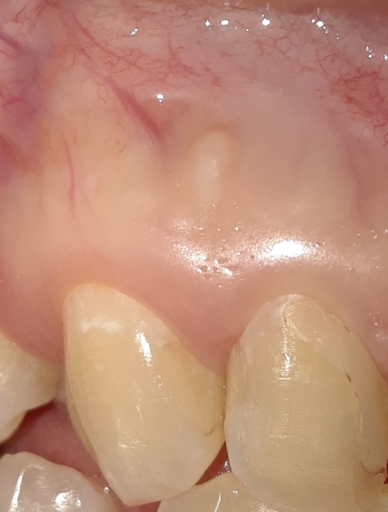

Hi, I will have my upper left premolar extracted tomorrow due to an abscess. I was wondering why an antibiotic cannot be injected on the site and treat the infection around the root instead of removing the tooth. I will be left with a huge gap because my molar was wrongly extracted since the dentist assumed the pain was coming from a sensitive nerve (it was alive) last year but now it seems the problem was the premolar which is with a crown and had a root canal. They also performed my sinus (OC) and now the risk of happening the same is very high. I cannot see a specialist who will do re-root canal to try to save my tooth. Please can you help me with an advice how to preserve my tooth? Why injecting antibiotics is not usually considered? Is it because the bacteria make a biofilm and cannot be targeted? Thank you!